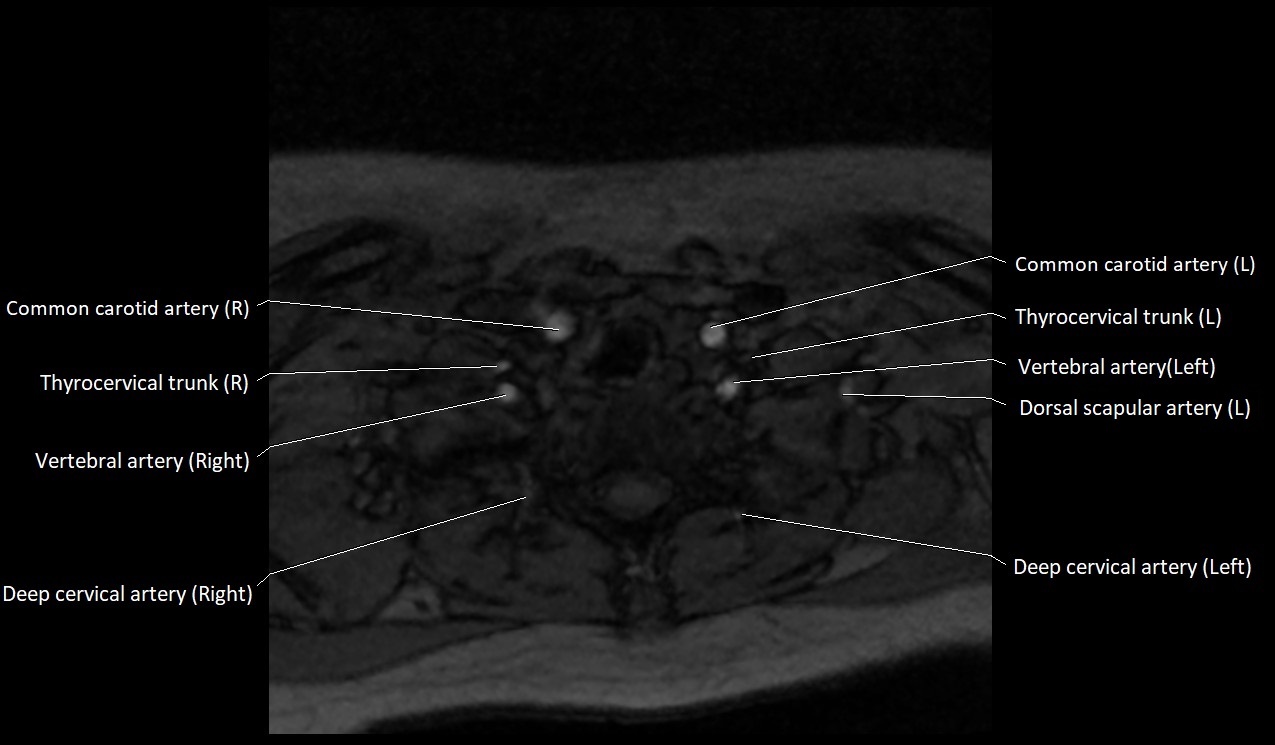

MRI images

image